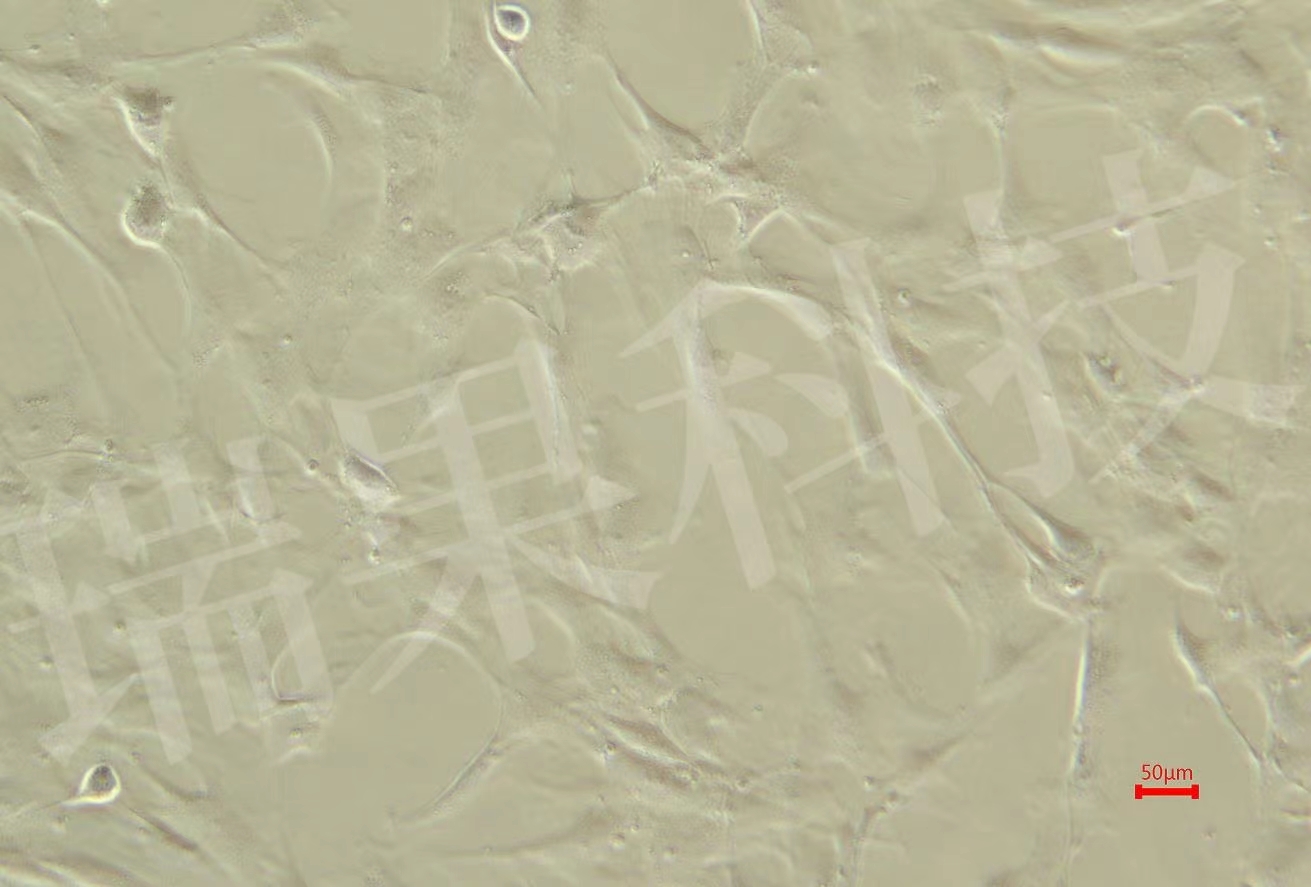

HK2